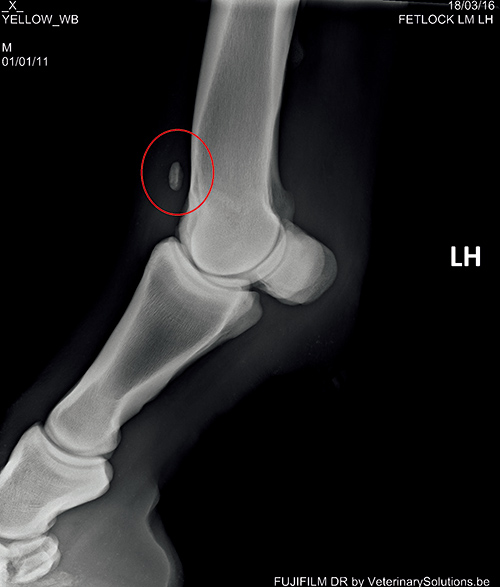

診斷和治療臨床獸醫(yī)可以通過臨床癥狀作出初步診斷。確診需要做 X 線片檢查。

例如上圖中紅圈內(nèi)是一塊很明顯的游離于球節(jié)的骨軟骨碎片??梢圆捎藐P(guān)節(jié)鏡做進(jìn)一步檢查,以確定關(guān)節(jié)的損傷程度,并通過微創(chuàng)手術(shù)去除軟骨碎片,如上圖。在國外,馬主通常會(huì)在馬匹三、四歲的時(shí)候請(qǐng)獸醫(yī)做一次全面的 X 線片檢查來評(píng)估它們的關(guān)節(jié),一旦發(fā)現(xiàn) OCD,及早進(jìn)行手術(shù)能最大程度減少其對(duì)關(guān)節(jié)的損傷,保住馬兒未來的運(yùn)動(dòng)生命。